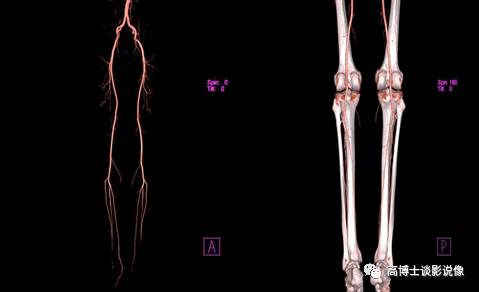

九、双下肢血管VRT重建

下肢血管VR重建可整体、直观的显示下肢血管的解剖结构及有无变异情况。